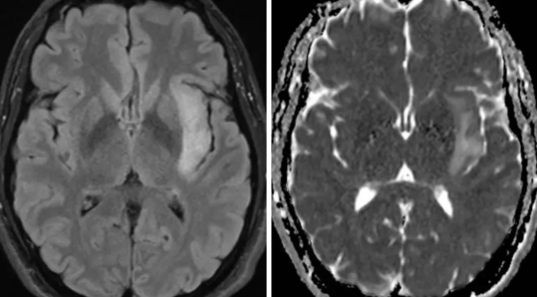

弥漫性星形细胞瘤属于WHO Ⅱ级,分化程度较高、生长缓慢。发病年龄集中于青壮年,男性发病率高于女性,该病变好发位置在中枢神经系统的任何部位,以大脑半球多见,多累及额、颞叶。手术切除是目前较好的治疗选择。

MR平扫可见边界模糊异常信号灶,少部分边界清晰者可见类圆形肿块影,T1WI序列可见等/低信号,T2WI序列可见高信号,病灶内信号不均匀,可伴囊变信号影,病变周围少有水肿,占位效应轻;增强扫描后病灶强化不明显,或仅可见轻中度强度表现,以小片状、环状及结节状强化多见,伴囊变患者多可见非规则环形强化。